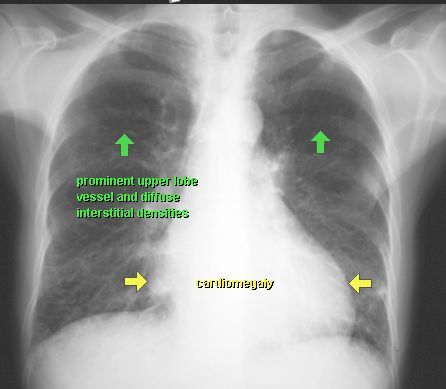

OBRZĘK PŁUC

RTG